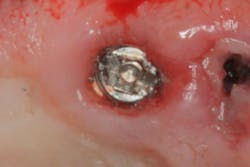

With a high-speed handpiece equipped with a diamond bur, prepare a 1 mm slot across the most occlusal portion of the broken screw fragment (figure 2). Follow this process:

- Hold the handpiece firmly to avoid having the bur inadvertently jump into the implant body. Use an appropriate-sized mini flat-end screwdriver and reverse out the screw. Brånemark systems have a screwdriver like this, or you can purchase one at a local hardware store.

- A low-speed contra-angle handpiece with a one-quarter round carbide bur running in a reverse mode could help spin out the screw. The small round drill acts as a screwdriver and holds the head of the fragment.8